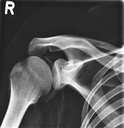

Dieses weltweit einmalige Phantom bietet erstklassige Übungsmöglichkeiten für die Lagerungs- und Einstelltechnik in der Projektions-Radiographie und gehört eigentlich zur Grundausstattung jeder Röntgen-Ausbildungsstätte. Das Phantom enthält ein natürliches menschliches Skelett sowie die Umrisse von Kehlkopf, Lunge, Herz und Nieren (Organe erscheinen als Schatten auf den Röntgenbildern), dadurch können mit dem Phantom echte Röntgenaufnahmen wie beim Patienten gemacht werden. Durch die Verwendung des echten Skeletts können Leitstrukturen im Knochen erkannt werden, was bei Kunststoffskeletten nicht möglich ist. Bei der Montage des Phantoms wird besonderer Wert auf die Darstellung der Gelenkspalte gelegt. Die Gelenke sind voll beweglich montiert, und ermöglichen die Lagerung in den normalen Röntgenpositionen (z.B. Froschposition, Pro- und Supination des Unterarms). Die Arme können nach oben bewegt werden, so dass das Modell auch für alle knöchernen Untersuchungen im CT verwendet werden kann. Bei jedem Phantom handelt es sich um ein handgefertigtes Unikat, welches sich in Größe und Ausführung unterscheiden kann. Je nach Modell können pathologische Befunde vorhanden sein, die äußere Erscheinung kann sich je nach Größe des Modells unterscheiden. Die neue Ausführung dieses Modells wurde in Zusammenarbeit mit einer namhaften deutschen Schule für Med. Techn. Radiologieassistenten komplett überarbeitet und erfüllt alle Anforderungen für die Ausbildung. Der Verkauf dieses Phantoms erfolgt nur gegen Nachweis der medizinischen Verwendung. Natürliche Größe.